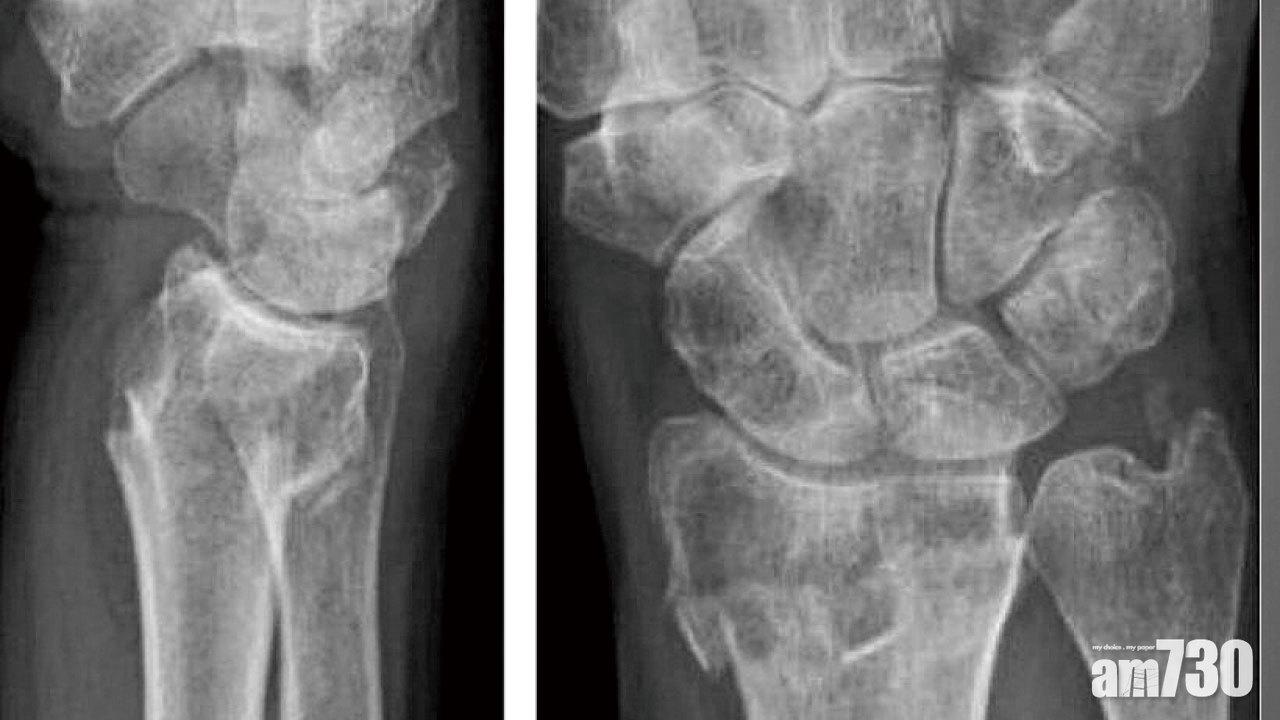

「清姐,跌咗好多喎,最新報-3.3!」清姐聽後忽然感觸落淚,哽咽地應道:「跌得好慘!」「清姐,唔好咁啦!只要你肯堅持唔放棄,終有一日返家鄉㗎!」原來,故事中年過六十的清姐,早年做身體檢查時,已得知患上骨質疏鬆,但她卻置之不理,不肯接受藥物治療。直至最近不幸在街上跌倒,導致手腕骨折而須做手術。及後再次檢查骨質密度,才發現T值已由-2.8跌至-3.3的「歴史新低」。雖今次她跌至「損手」,但骨質疏鬆所引致的脆性骨折,其實可以有效地「對沖」和「避險」。

骨質密度檢測包括坊間用作簡單篩查的超聲波,以及醫生用作診斷的雙能量X光吸收儀(DEXA)。而DEXA報告內的T值,若為-1(統計學上的一個標準差)或以下,則屬於骨質量偏低(Osteopenia)。如達至-2.5或以下,便證實患上骨質疏鬆(Osteoporosis)。骨質密度,猶如一間經營骨骼健康的上市公司之「股價」。當「股價」到達成年高增長的巔峰後,便隨着鈣質流失而出現「轉勢」。女性在更年期後,女性荷爾蒙分泌減少會令鈣質加速流失,「股價」也進一步下挫「尋底」。萬一發生脆性骨折,在技術上已可界定為進入骨質疏鬆的「熊巿」。